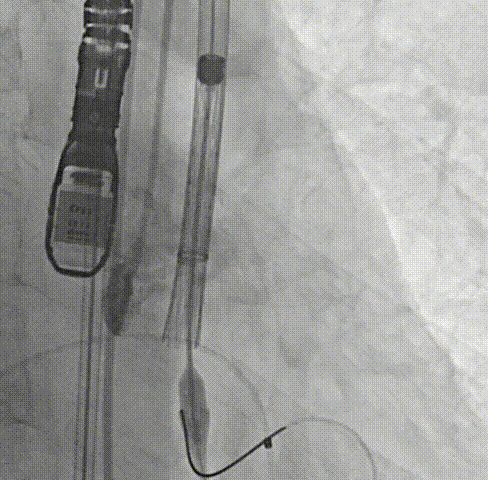

周达新教授 复旦大学附属中山医院 共识引路,干瓣启新,共赴临床解决方案:当前,结构性心脏病的介入治疗已迈入微创化、精准化的新时代。技术的革新、创新器械的上市,都是我们中国技术领跑的印证,《专家共识》的应运而生是中国医生对于行业“规范化”的践行,让治疗更精准、让医者更贴近“以患者为中心”的医疗本质。 潘文志教授 复旦大学附属中山医院 严谨求真重思考 创新临床互验证:在医学的漫长征途中,新器械的突破与严谨的临床研究是两大核心驱动力。拥抱创新的同时需要严谨求证,预装干瓣作为创新器械,其即取即用的特性可以很好的适配“急诊”的场景,此外,国产创新不是简单的复制,干瓣的瓣叶质地不是字面意思“干”的,而具“曲柔性”。所以,需要多看多测,才能全面了解一款产品。《经导管心脏瓣膜治疗术》的问世也是凝结着我们带着临床思维思考的结晶的“独家秘笈”,希望能够将“来时的路”变成未来行业同行者的“高效学习之路”! 患者病史 多病共存陷困境,主动脉瓣狭窄成 “首要威胁” 现病史:患者反复活动后胸闷2年余,无胸痛、心悸,无头晕、晕厥等不适,未予重视。患者轻微体力活动(快走、爬楼梯)即胸闷气促,静息及夜间无不适,无咳嗽、心悸等症状。为进一步诊疗收入我科,患病以来精神、食欲、睡眠、二便及体重均正常。 既往史: 2025年5月7日因小便不畅至外院住院病理穿刺确诊前列腺癌,期间检查心超提示主动脉瓣钙化伴重度狭窄,遂暂缓前列腺手术。2025年05月30日至我院就诊。 2025年5月20日开始服用比卡鲁胺片。患者血脂异常,长期服用丹参滴丸,麝香保心丸,心通颗拉。 手术史外伤史:10年前行肺手术,具体不详。否认外伤史。 入院检查 心电图提示:窦性心动过缓;ST-T改变; 心超显示:主动脉瓣钙化伴重度狭窄及轻度反流,Vmax 4.8m/s、PGmax 93mmHg、PGmean 47mmHg;左房增大,左室壁增厚。 冠状动脉CT造影:左前降支中段浅表心肌桥,主动脉瓣增厚伴重度钙化,主动脉粥样硬化。 术前CT 三叶瓣,中度钙化,主动脉根部直径25.4mm,LVOT直径23.5mm 双侧冠脉开口高度尚可,瓦氏窦尚可,ST尚可,升主尚可,冠脉风险小;中度钙化,心脏角度39.2°;心腔内径可,左室壁增厚。 外周走行尚可,全主动脉存在散在钙化,右侧穿刺点需避开钙化,血管内径可,血管内壁存在纤维增厚。 手术策略:右侧股动脉为主入路,使用20F大鞘;20球囊预扩,植入AV29瓣膜; 手术过程 主动脉根部造影 输送系统柔顺过弓 定位 缓慢释放瓣膜 造影观察 稳定脱钩 最终造影性钙位置良好,轻微瓣周漏 术后超声:轻度瓣周漏,术后平均压差11mmHg 出院前超声:平均压差11mmHg 在多基础疾病患者日益增多的当下,该病例也为临床提供重要启示:针对合并肿瘤、既往手术史的复杂瓣膜病患者,需通过多学科协作(心内科、肿瘤科、麻醉科等)全面评估病情,结合精准影像技术与适配器械,制定个体化手术方案,才能在保障安全的同时,实现最优疗效。 作为中国结构性心脏病领域的标杆学术活动,中国结构周 2025为这类高水平临床病例提供了交流平台,助力推动我国结构性心脏病诊疗技术持续创新,让更多复杂瓣膜病患者受益于精准医疗方案。 ProStyle A®预装干瓣——助力临床最优化解决方案: 轻松过弓,精准可控:该病例全主动脉存在散在钙化,右侧穿刺点需避开钙化,ProStyle A®较细的尺寸+柔顺的输送系统通过性能得到了很好的验证; 平稳释放:平衡的径向支撑力降低了释放过程中的张力,流入端小锥角设计能够迅速锚定贴边; 预装干瓣 便捷顺安:金仕生物专利抗钙化技术运用纳米技术去除组织内的细胞碎片和磷脂,封闭游离醛基,从根本上阻断了瓣膜钙化的多项因素,显著提升了瓣膜的耐久性;同时,相比较传统戊二醛保存方式,干式存储最大限度的保留心包的亲水亲油平衡,还原组织天然曲柔性,进一步保障了瓣叶开合,保证长期耐久性; 专家简介 葛均波 复旦大学附属中山医院(点击查看专家详细简历) 周达新 复旦大学附属中山医院(点击查看专家详细简历) 潘文志 复旦大学附属中山医院(点击查看专家详细简历) · END ·